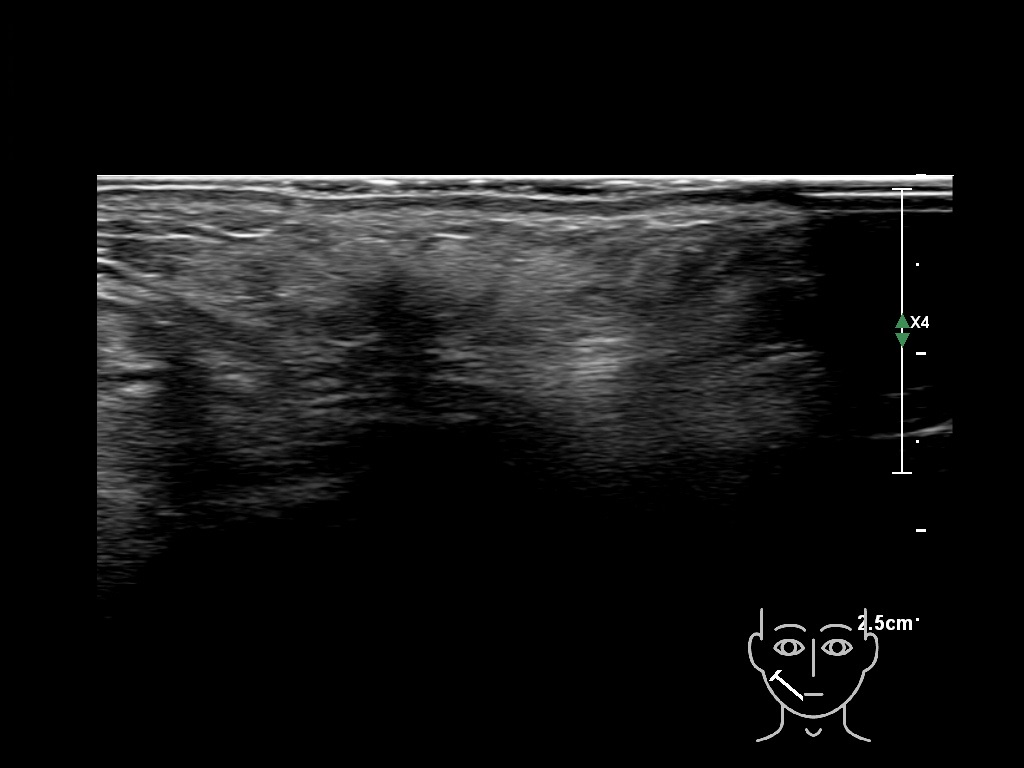

Fillers

Draw in the second image below where the fillers are located. To check if your answer is correct, swipe the first image to the right.